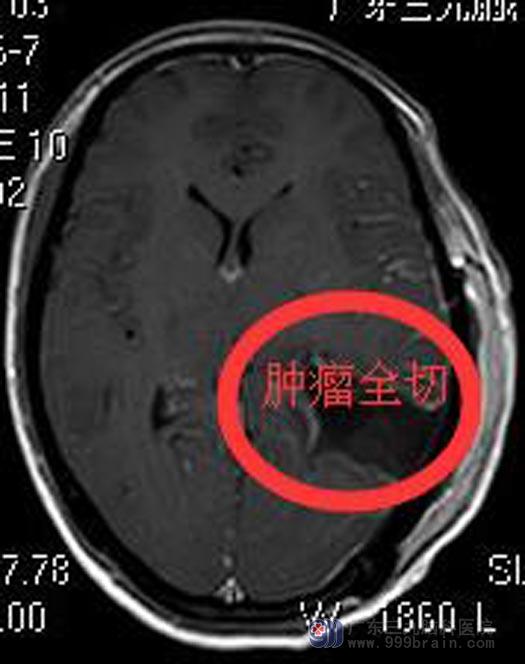

完善术前检查后,鲁明主任主刀,在全麻下行左侧脑室后角占位切除术,术中显微镜下见灰白色肿瘤组织,肿瘤质脆,血供丰富,边界清晰;镜下用激光刀分块全切除肿瘤,手术经过顺利。术后,阿香头痛症状好转,康复出院。病理回报:脑膜瘤,纤维细胞型,WHO I级。